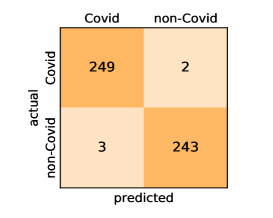

Here, we present and discuss the obtained results for detecting COVID-19 on the considered CT image datasets with different deep networks. We report the quantitative results along with the confusion matrices for every single architecture of the adopted networks.

On the SARS-CoV-2 CT dataset, ResNet101 achieves the best overall performance with respect to almost all evaluation metrics, with an average accuracy and F1-score of and , respectively. The model also achieves an average sensitivity rate of indicating that, on average, only two COVID-19 images are falsely predicted as negatives. It is also powerful enough to correctly identify all Non-COVID-19 cases with only one false positive resulting a specificity rate of . The highest sensitivity score of is achieved by the InceptionV3 model, where only one COVID-19 image is falsely predicted as negative on average. The SqueezeNet model obtains the lowest performance with respect to all evaluation metrics with a fairly acceptable average accuracy and sensitivity scores of and , respectively. Also the ShuffleNet architecture obtains satisfactory performance with approximately improvements on average for all metrics compared with SqueezeNet. Although the results obtained by these models are inferior compared with the rest of models, but they are more efficient. This matches their main objective of reducing the computational costs rather than improving their visual recognition abilities. The rest of models achieve competitive performance and very promising results with slight performance differences. Comparing the different variants of ResNet and DenseNet, we can see that the deeper variants from each architecture yield a slightly better performance. The deeper ResNet101 and ResNeXt101 show a marginal gain in performance compared with their shallower counterparts. The details about class-wise results for each model are summarized in the confusion matrices in Figure 9.

Our models achieve fairly good performance compared with the recently published work using the exact network architectures. This can bet attributed to a better optimization of our models and the effectiveness of our fine-tuning strategy using custom-sized inputs determined specifically for each architecture. Here, we see that DenseNet201 outperforms all other architectures. The model achieves average accuracy and sensitivity scores of and , respectively. It also identifies all COVID-19 images with only four images, on the average, are falsely predicted as Non-COVID-19. DenseNet169 achieves the second best average accuracy of and a very high sensitivity identical to the best model. The DenseNet121 and Xception models have nearly identical results for all evaluation metrics. We observe that small-sized networks such as ResNet18 achieves comparable results with other deeper models. The SqueezeNet and ShuffleNet models perform at a similar level of accuracy. The variants of the ResNeXt models have comparable results and perform as good as the different ResNet variants. A detailed analysis on the class-wise results for individual models is presented in the confusion matrices in Figure 10.